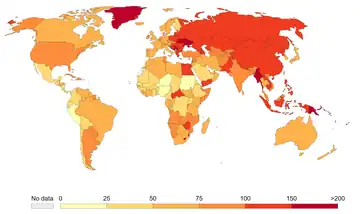

Mortality

Smoking is the cause of about 5 million deaths per year.[52] This makes it the most common cause of preventable early death.[53] One study found that male and female smokers lose an average of 13.2 and 14.5 years of life, respectively.[54] Another measured a loss of life of 6.8 years.[55] Each cigarette that is smoked is estimated to shorten life by an average of 11 minutes, though this may vary slightly on the contents and brand.[56][57][58] At least half of all lifelong smokers die early as a result of smoking.[35] Smokers are three times more likely to die before the age of 60 or 70 than non-smokers.[35][59][60]

In the United States, cigarette smoking and exposure to tobacco smoke accounts for roughly one in five,[61] or at least 443,000 premature deaths annually.[62] To put this into context, ABC's Peter Jennings (who would later die at 67 from complications of lung cancer caused by life-long smoking) famously reported that in the US alone, smoking tobacco kills the equivalent of three jumbo jets full of people crashing every day, with no survivors.[63] On a worldwide basis, this equates to a single jumbo jet every hour.[64]

A 2015 study found that about 17% of mortality due to cigarette smoking in the United States is due to diseases other than those usually believed to be related.[65]

It is estimated that there are between 1 and 1.4 deaths per million cigarettes smoked. In fact, cigarette factories are the most deadly factories in the history of the world.[66][67] See the below chart detailing the highest-producing cigarette factories, and their estimated deaths caused annually due to the health detriments of cigarettes.[66]